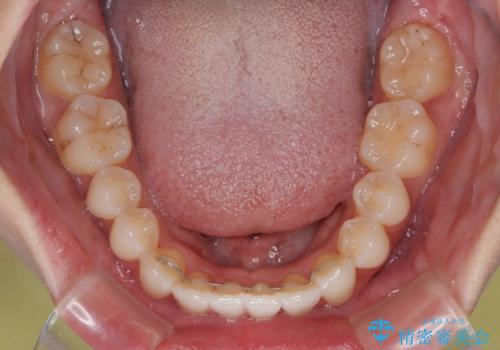

上下前歯の突出感とデコボコを気にして来院された患者様です。

インビザラインによる上下歯列の側方拡大と後方移動、必要に応じてIPR(歯と歯の間を削る)によりスペースの獲得により歯列を整えることとしました。

治療途中、出産や転居があり、2年ほど治療期間が長くなってしまいましたが、前歯の歯並びや飛び出した感覚を無事に改善させることができました。